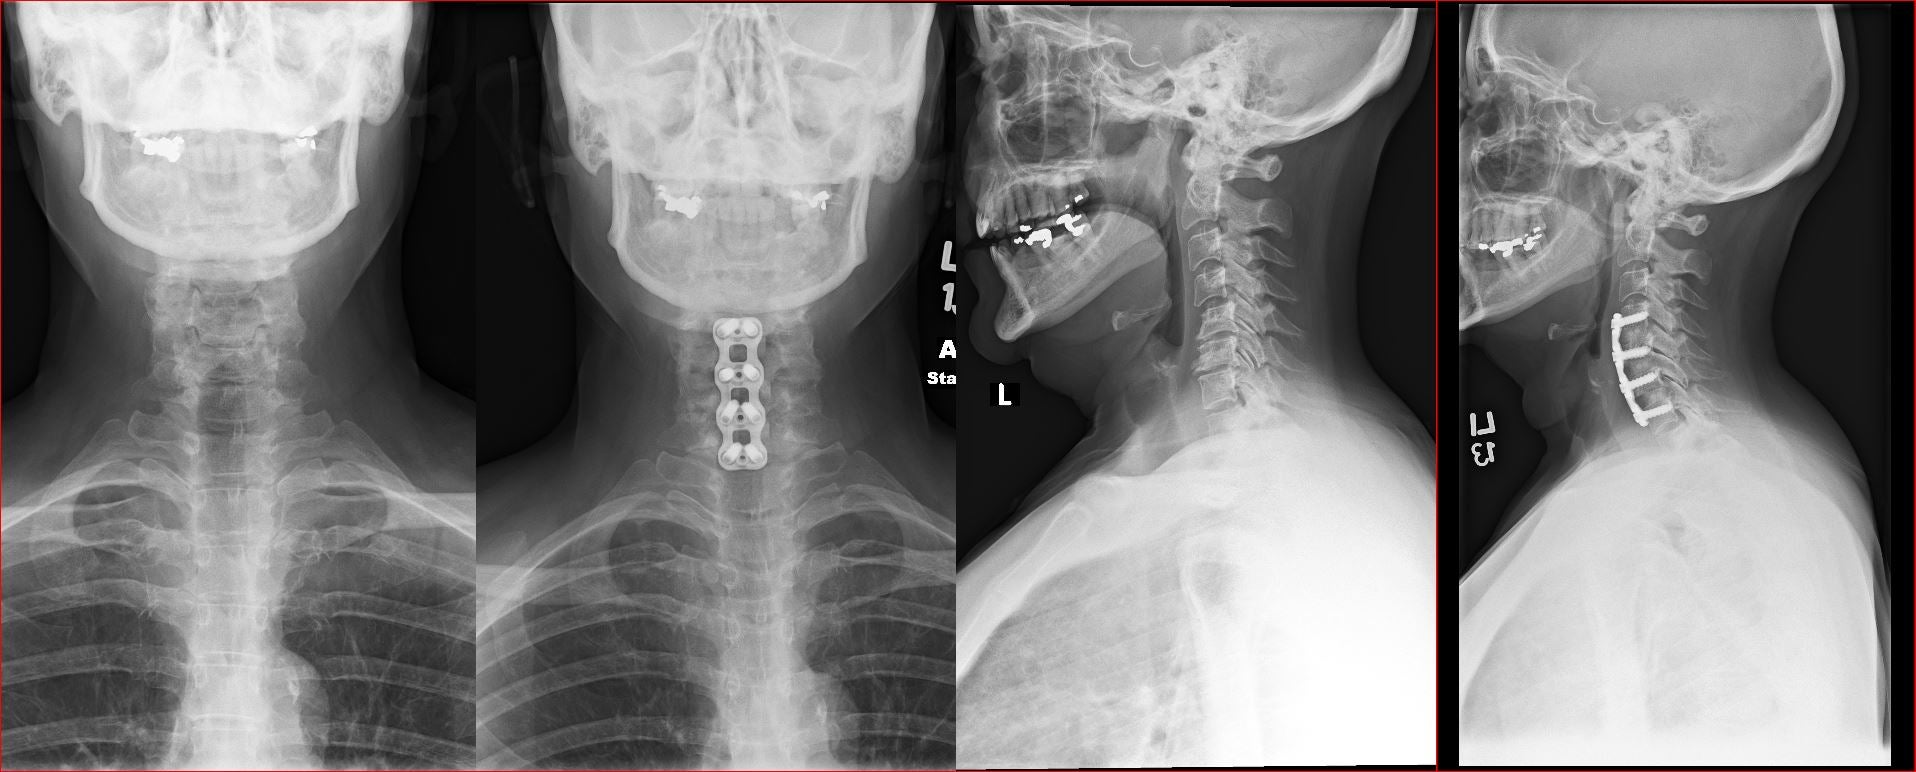

Anterior Cervical Spine Surgery

Cervical Disc replacement

Anterior Fusion

Corepectomy